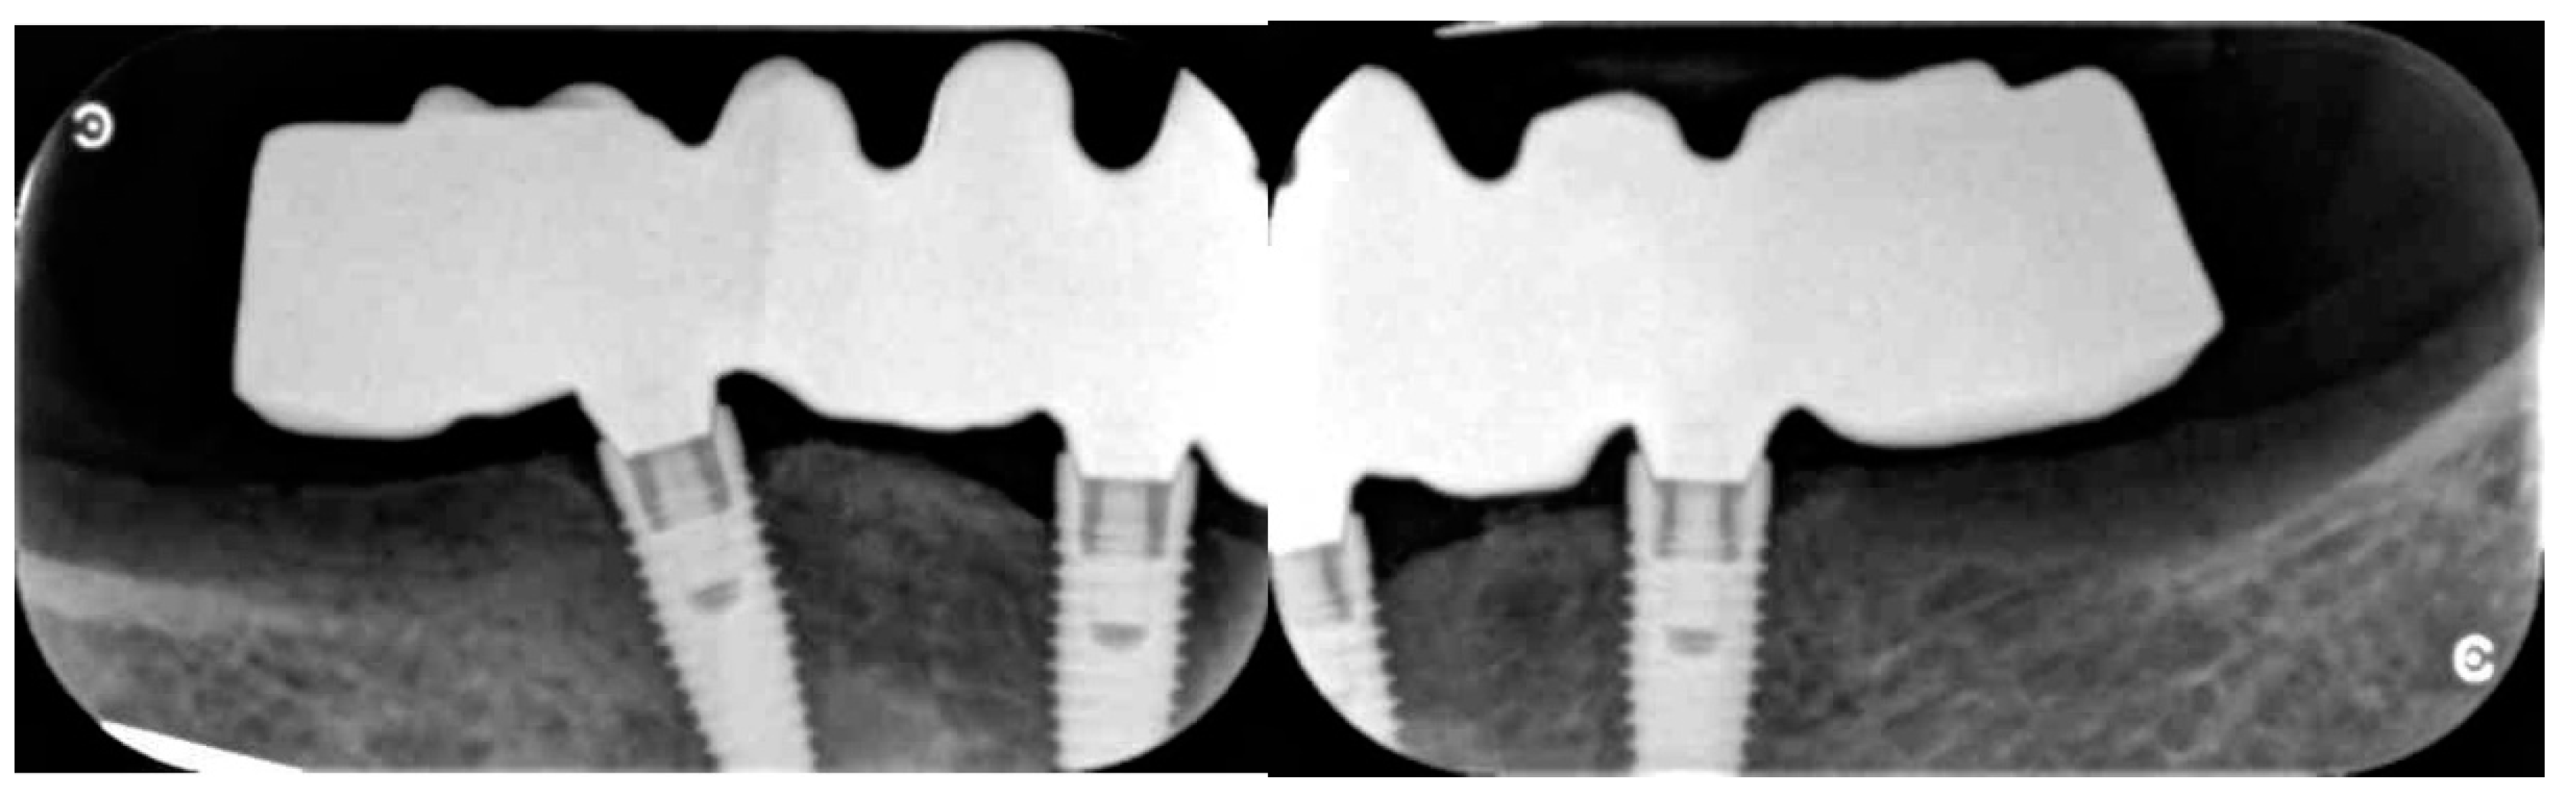

- Peri-implant bone levels changes were measured as the distance between mesial and distal margin of the implant neck (inserted slightly below buccal bone level) to the most coronal point where the bone looked to be in contact with implant. Mean values of mesial and distal measurements were calculated for each implant. Measurements on digital periapical radiographic images, obtained by parallel cone technique with extension cone paralleling instrument (Rinn XCP, Dentsply, Elgin, IL, USA), were taken after implant placement (baseline) and three years after final loading. All radiographs have been analyzed through a software (DFW2.8 for Windows, Soredex, Tuuka, Finland), calibrated for each image using the known distance between two implant threads’ consecutive steps. In case of an unclear image, the radiograph was taken again. A dentist, not previously involved in this study, performed every radiographic measurement.